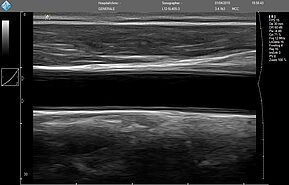

Исследование FAST (Сфокусированная сонографическая оценка при травме) позволяет выявить наличие жидкости в предполагаемых клинических условиях, визуализируя 10 структур или пространств в четырех областях:

E-FAST (расширенный-FAST) дополнительно обследует переднюю и боковую плевральную полость (торакальная проекция) для оценки наличия пневмоторакса или плеврального выпота, предположительно гемоторакса у пациентов с травмой.